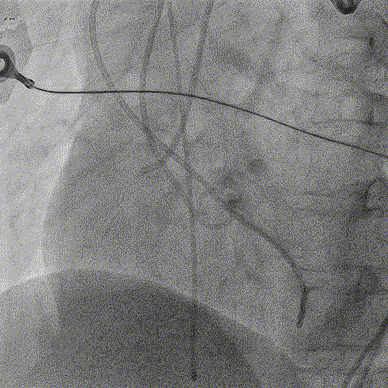

术前CT分析右侧的冠脉风险较高,球囊预扩前右冠开口处预放一个冠脉保护支架,采用18mm球囊预扩,有轻微腰征,无造影剂渗漏;

右侧冠脉保护准备

球囊预扩

TaurusElite输送系统轻松过弓、跨瓣,AV23瓣膜瓣环上约2mm释放;

TaurusElite轻松过弓

瓣膜释放

释放到工作位后多角度观察左右冠脉血流灌注情况、瓣膜释放形态及植入深度,确认没问题后再缓慢脱钩完全释放,最终造影显示瓣膜形态、位置良好,冠脉血流灌注正常,微少量瓣周漏;